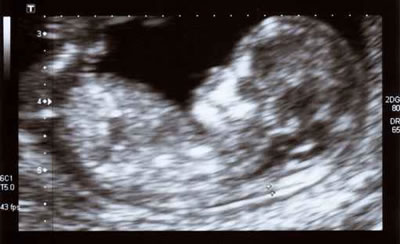

Recomendações de vigilância da gravidez da Sub-Região de Saúde do Porto